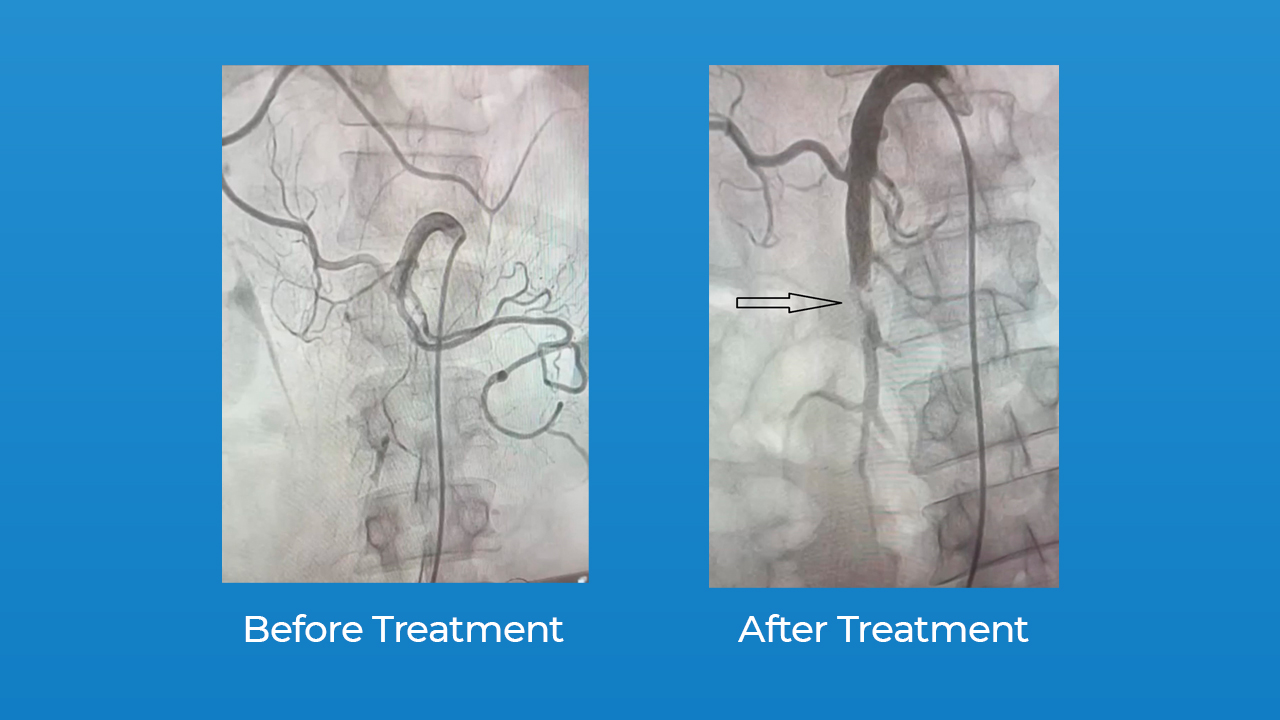

Catheter direct thrombolysis of occluded SMA Trust Multispeciality Catheter Directed Thrombolysis Guidelines    here we summarize the 2019 esc guidelines for the diagnosis and management of acute pe, which were.   for patients with extensive dvt in whom thrombolysis is considered appropriate, the ash guidelines suggest.  this article will present the results of recent clinical trials, updated clinical practice guidelines, and evolving clinical practice,.   this review offers the reader an. Catheter Directed Thrombolysis Guidelines.

Catheter direct thrombolysis of occluded SMA Trust Multispeciality Catheter Directed Thrombolysis Guidelines   this article will present the results of recent clinical trials, updated clinical practice guidelines, and evolving clinical practice,.   for patients with extensive dvt in whom thrombolysis is considered appropriate, the ash guidelines suggest. With extensive dvt, the benefits of catheter.   this review offers the reader an update on the results of recently completed clinical trials,.   here. Catheter Directed Thrombolysis Guidelines.